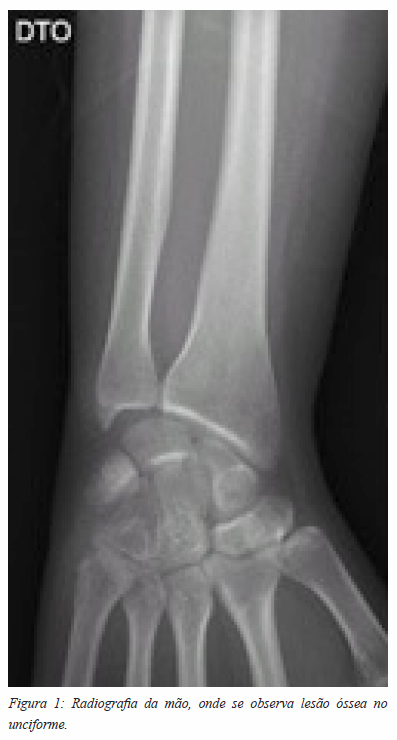

Apresentava radiografia (Figuras 1 e 2) com lesão lítica do unciforme, com esclerose dos bordos, sem disrupção da cortical, que ocupava cerca de 30% do osso. Foi pedida uma TC, que revelou uma lesão ocupando espaço do unciforme.

A hipótese diagnóstica, pela aparente não agressividade da lesão e dada a elevada prevalência, era a de um encondroma. Foi submetida a cirurgia de remoção da lesão. Por via dorsal, foi curetada a lesão com colocação de enxerto esponjoso de ilíaco e fosfato de cálcio. A recuperação decorreu sem intercorrências, com recuperação progressiva da mobilidade do punho. O controlo radiográfico da cirurgia está ilustrado nas figuras 3 e 4.